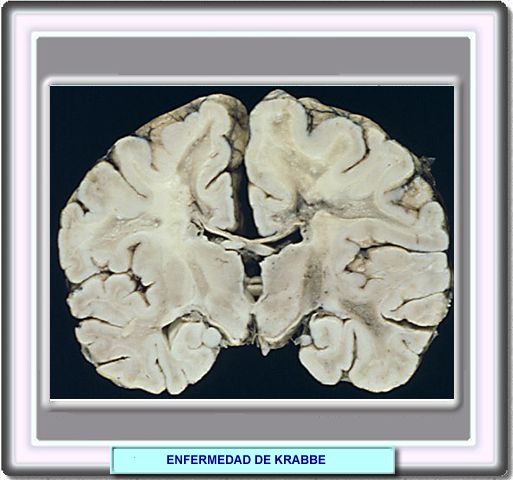

También denominada leucodistrofía de células globoides, la enfermedad de Krabbe es una enfermedad hereditaria por depósito lisosomal debida a la deficiencia de una enzima, la galactosilceramidasa, responsable de la hidrólisis varios galactolípidos incluyendo la galactosilceramida y la psicosina.

El gen que codifica esta enzima se localiza en el cromosoma 14q21-q3. Se conocen al menos 40 mutaciones de este gen.

El funcionamiento deficiente de la galactosilceramidasa produce la acumulación de ceramidas en las células nerviosas que adquieren un aspecto globoide